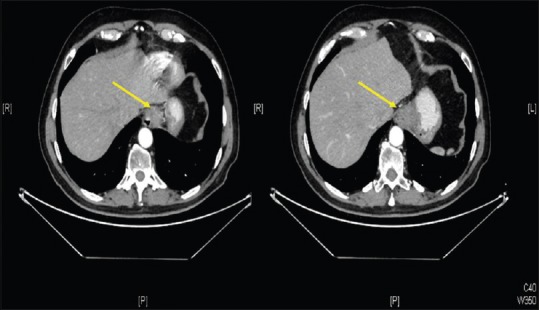

食管癌最常见的表现是腺癌和鳞状细胞癌。近年来,后者的发病率有所下降,增加了腺癌的发病率。目前,另一种发病率低得多的肿瘤被描述为具有神经内分泌成分和另一种外分泌腺成分的肿瘤,自2010年以来被归类为混合性腺神经内分泌癌(MANEC)。我们提出的情况下,68岁的男性消化不良和胃脘痛的历史后,进行胃镜检查,被诊断为恶性肿瘤的食道。患者行全食管切除术,经颈吻合术重建胃管状成形术。免疫组化后的最终结果显示,肿瘤由60%的腺癌成分和40%的与神经内分泌相容的成分组成。根据这些发现并根据世界卫生组织2010年的分类被诊断为食道MANEC。manec是一种罕见的肿瘤,发生在消化道的其他部位,食道是一个罕见的位置。其术前诊断困难,需要通过特异性免疫组织化学技术对完整片进行最终分析才能确定诊断。它的治疗基本上是手术,而化疗辅助治疗方案由于发病率低,目前还没有很好的定义。

The most frequent presentation of esophageal cancer is adenocarcinoma and squamous cell carcinoma. In recent years, the latter has decreased its incidence increasing the adenocarcinoma. Currently, another type of tumor with a much lower incidence has been described, which has a neuroendocrine component along with another exocrine glandular component and has been classified since 2010 as mixed adenoneuroendocrine carcinoma (MANEC). We present the case of a 68-year-old male with a history of dyspepsia and epigastric pain who after performing a gastroscopy, was diagnosed with a malignant neoplasm of the esophagus. The patient underwent a total esophagectomy with reconstruction by tubular gastroplasty with cervical anastomosis. The final result of the piece after immunohistochemistry revealed that the tumor was composed of one component of adenocarcinoma in 60% together with another component compatible with neuroendocrine in 40%. With these findings and according to the World Health Organization classification of 2010 was diagnosed as esophageal MANEC. MANECs are rare tumors, described in other locations of the digestive tract, the esophagus being an infrequent location. Its preoperative diagnosis is difficult, and it is not until the final analysis of the complete piece by means of specific immunohistochemical techniques when its diagnosis can be established. Its treatment is fundamentally surgical, whereas the adjuvant therapeutic schemes with chemotherapy are not well defined at present because of their low incidence.